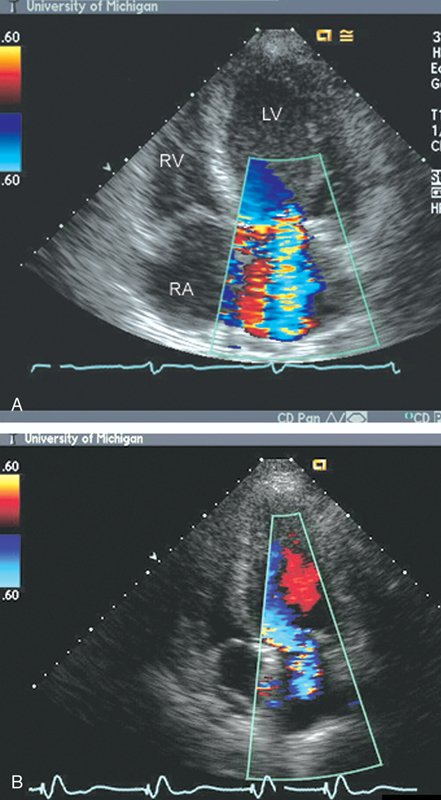

فحوصات تشخيصية لبعض امراض القلب والشرايين التاجية